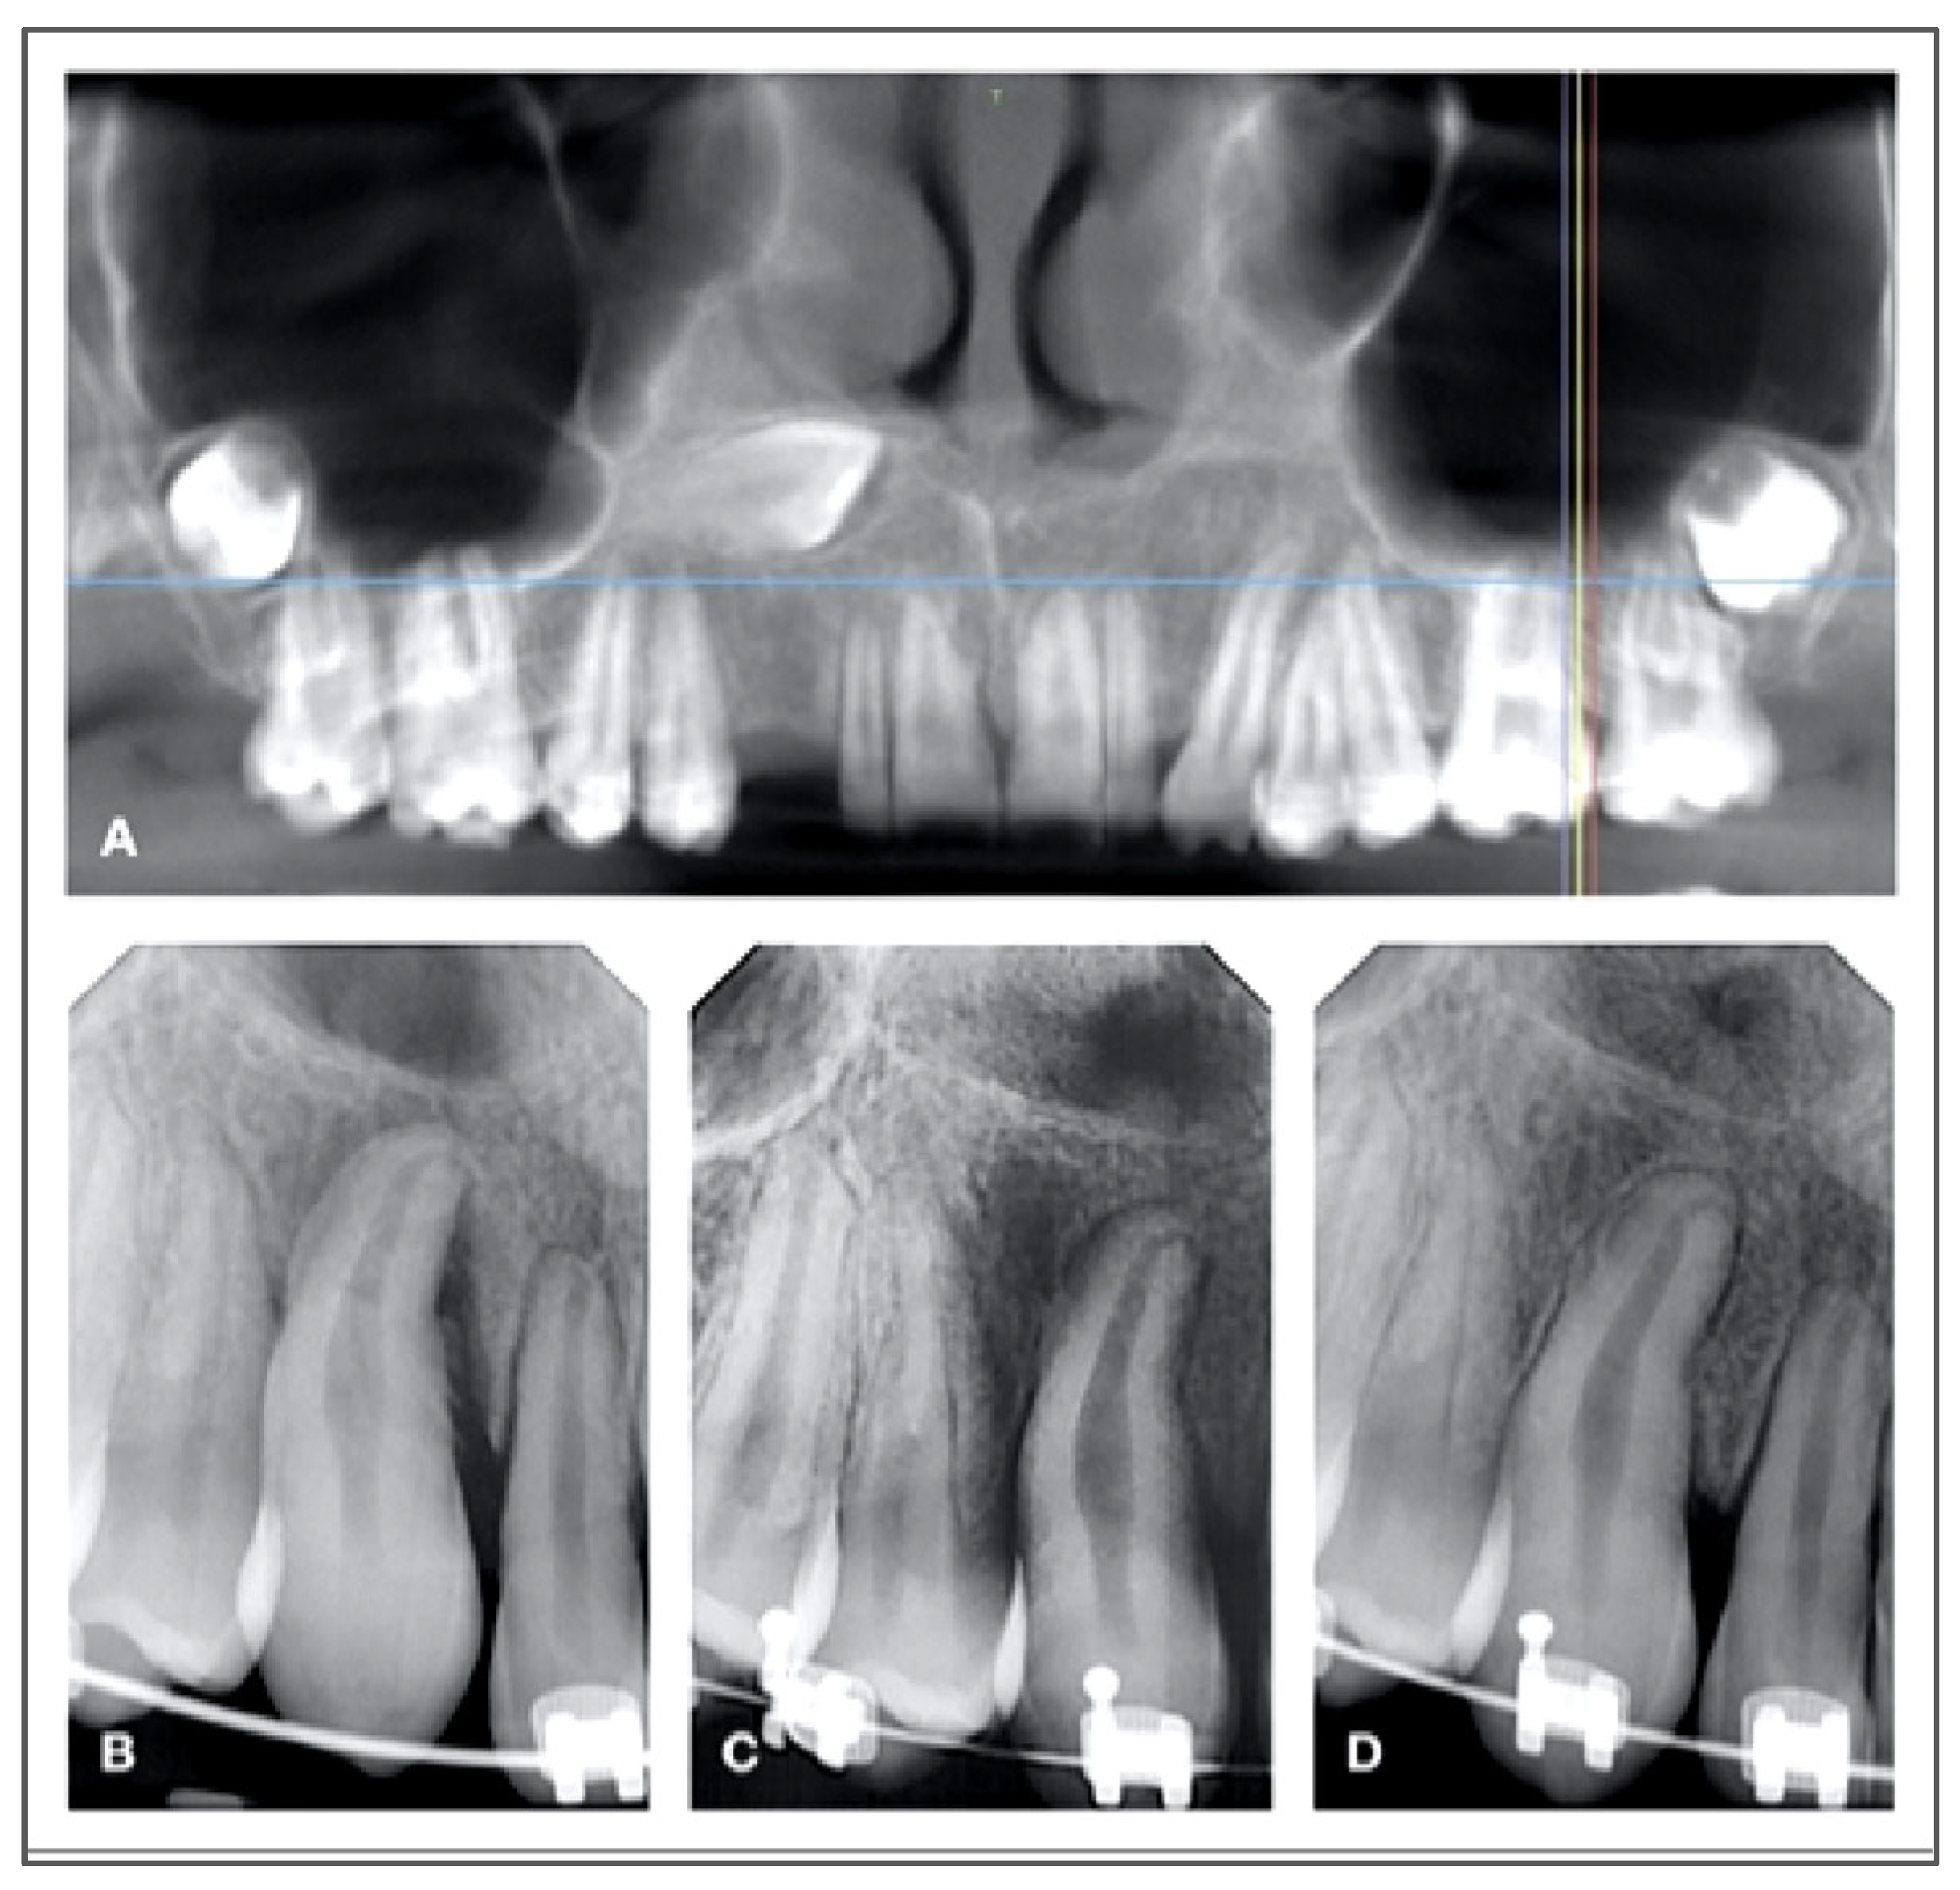

- Post-Operative Radiography: A periapical radiograph is obtained immediately after reimplantation to confirm accurate repositioning and stabilization.

7.2. Endodontic Considerations and Healing Dynamics

- Teeth with complete root development typically require root canal therapy within two weeks post-reimplantation. This is often accompanied by the placement of an interim calcium hydroxide dressing, which promotes an antimicrobial environment and aids in monitoring periodontal healing. To delay the root canal treatment, waiting for a better stabilization of the transplanted tooth, an extraoral apicoectomy has been suggested during the surgery, because it is a fast technique that allows an immediate seal of the canals [42]. New trends propose not to treat mature transplanted teeth, suggesting potential healing [30,31].

- Teeth with incomplete root formation (open apex) are monitored for signs of pulp revascularization. If reinnervation fails to occur or if clinical or radiographic indicators of inflammatory root resorption develop, endodontic treatment becomes necessary to preserve the tooth and surrounding structures.